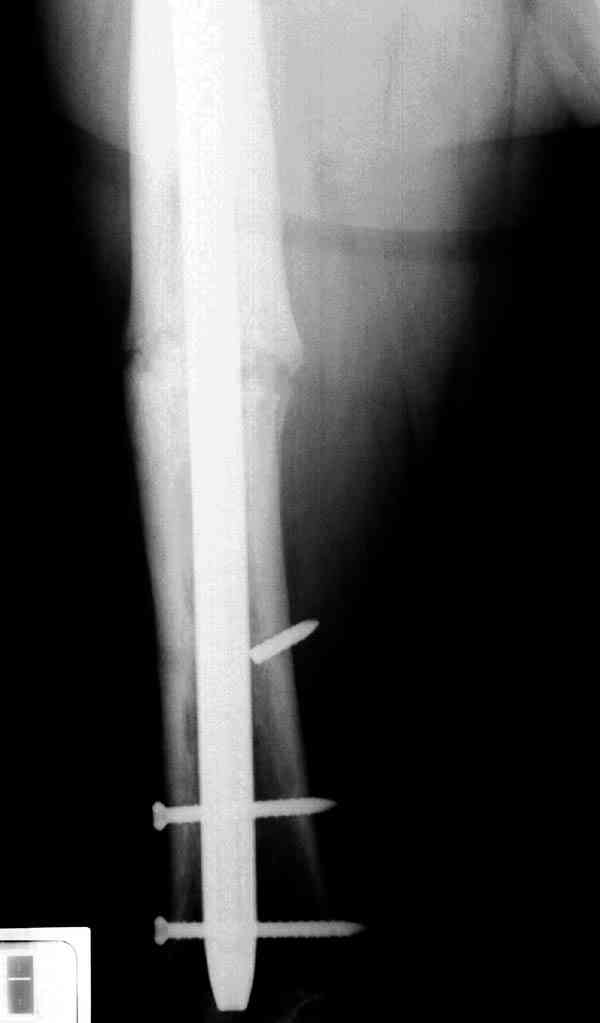

Уважаемые коллеги! У пациента 50-ти лет ложный сустав голени, перелом интрамедуллярного штифта. Перелому около 2 лет, ходить с полной нагрузкой начал через 3 мес. после операции. Боли при ходьбе почувствовал около 2 мес. назад. На данный момент ходит с полной нагрузкой без посторонней опоры. Среди коллег развернулась дискуссия по поводу способа оперативного лечения: -удаление штифта с перештифтовыванием блокированным штифтом с рассверливанием и остеотомией м\б кости -стабилизация зоны ложного сустава по медиальной поверхности LCP-пластиной с декортикацией или без -удаление штифта или без и синтез в АВФ с декотрикацией или без и остеотомией м\б кости

Наиболее быстро достичь опорности без боли и внешних приспособлений - удаление и блокируемый реостеосинтез с рассверливанием. Лучше бы тоже с

восстановлением оси (отклоняющая спица в дистальном отломке, чтобы новый стержень прошел не в старый канал, а кзади от него), еще и для создания дополнительного напряжения тканей в области несращения. Открывать зону несращения не надо.

Сросшаяся малоберцовая как распорка привела к образованию ложного сустава. В таких случаях удаляем сломанный штифт и проводим стимуляцию ложного сустава рассверливанием. Рассверливание канала создает стимуляцию на месте ложного сустава, и динамический вариант блокировки штифта с большим диаметром создаст стабильность. Ранняя нагрузка после остеотомии малоберцовой приведет к сращению ложного сустава.

Приспособление для удаления сломанных штифтов и наличие ЭОП облегчит задачу. При отсутствии крючка тогда можно применить обычный длинный ball pointed guide wire от интрамедулярного набора. Проволока, пропущенная за пределы гвоздя и зажатая другая вытащат сломанный конец штифта без проблем.